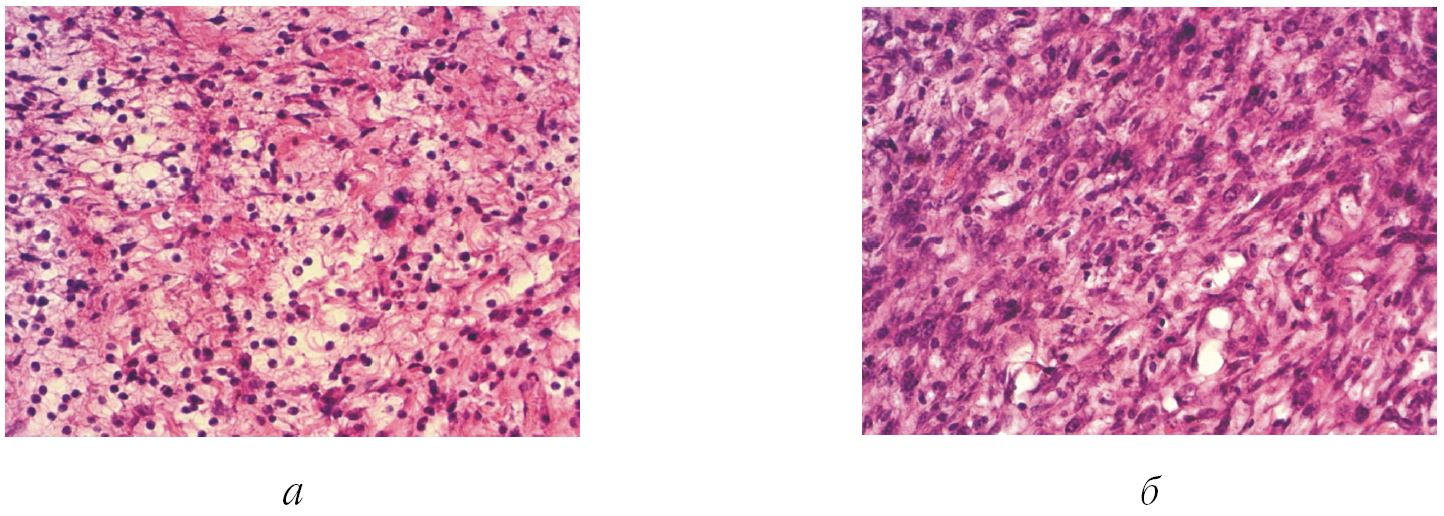

Результаты сравнительного исследования иллюстрированы рис. 2.

Рис. 2. Сравнительные данные гистологической картины в опытной и контрольной группах: а – контрольные данные. Грануляционная ткань. Лейкоцитарная инфильтрация. Окраска гематоксилином и эозином. Ув. х 400; б – испытуемый минеральный комплекс. Грануляционная ткань. Клеточный слой с фибробластами. Окраска гематоксилином и эозином. Ув. х 400